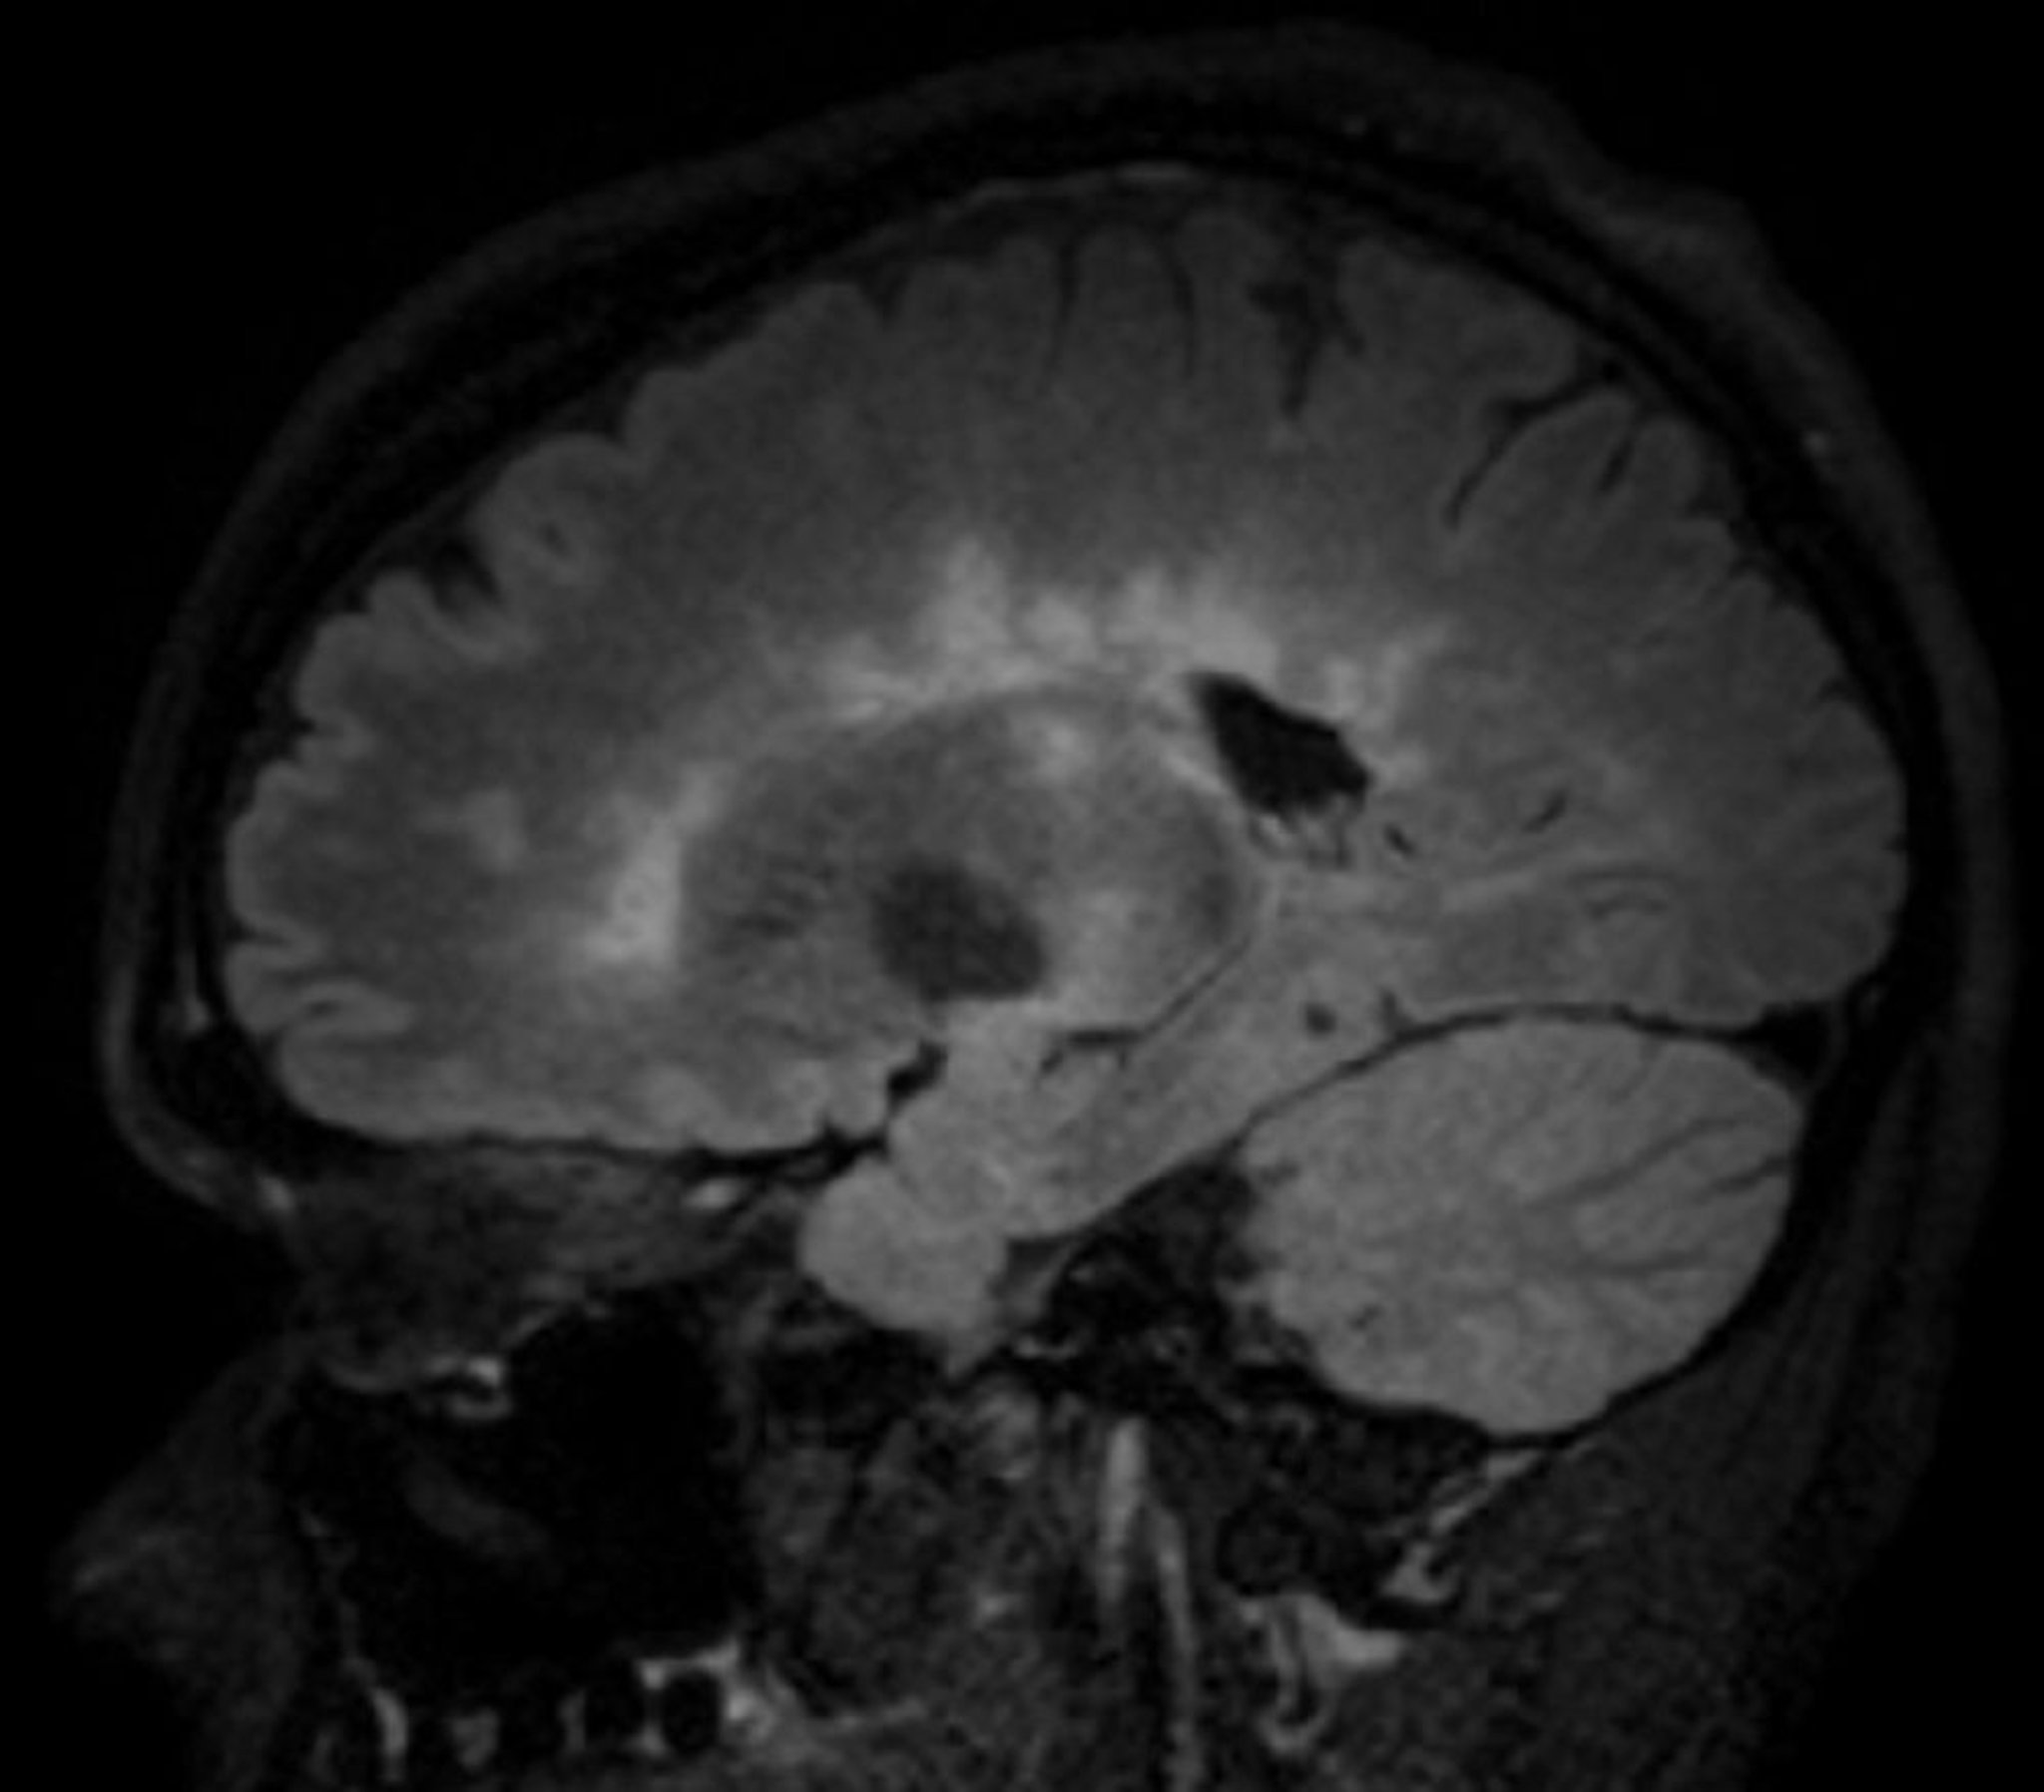

MRI is the most sensitive imaging test for MS and can exclude other treatable disorders that may mimic MS, such as nondemyelinating lesions at the junction of the spinal cord and medulla (eg, subarachnoid cyst, foramen magnum tumors). Gadolinium contrast enhancement can distinguish actively inflamed from older plaques. Also, higher-field MRI magnets (3 to 7 Tesla) can distinguish perivenular MS plaques from nonspecific white matter lesions.

• MRI that shows simultaneous enhancing and nonenhancing lesions, even if patients are asymptomatic

• Periventricular: ≥ 1 lesions (2)

• Cortical/juxtacortical (white matter next to cortex and/or cortex): ≥ 1 lesions

• Infratentorial: ≥ 1 lesions

• Spinal cord: ≥ 1 lesions

• Optic nerve: ≥ 1 lesions (either by MRI or clinical evaluation)